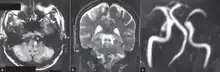

-

The three major arteries of the cerebellum: the SCA, AICA, and PICA. (Posterior inferior cerebellar artery is PICA.) -

Human brainstem blood supply description. PICA is#12.